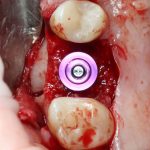

Глянем на то, что получилось:

Осталось адаптировать костный блок (убрать острые края), проверить его фиксацию и, при необходимости, добавить винты. Десятисекундное дело.